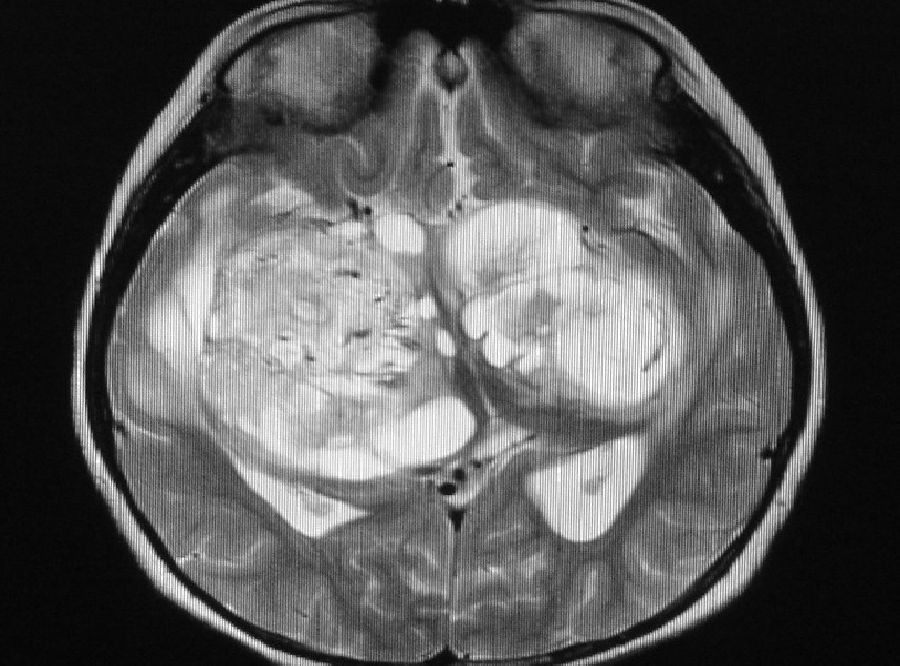

Investigadores de la Universidad de Uppsala, en Suecia, han descubierto en pacientes con cáncer cerebral unas estructuras similares a los ganglios linfáticos, donde las células inmunitarias pueden activarse para atacar el tumor. También han descubierto que la inmunoterapia potencia la formación de estas estructuras en un modelo de ratón.

En el estudio los investigadores describen su descubrimiento de estructuras similares a los ganglios linfáticos en el cerebro donde los linfocitos T podrían activarse.

"Estas estructuras se conocen como estructuras linfoides terciarias (TLS) y no se encuentran en individuos sanos --prosigue--. Tienen todos los componentes necesarios para favorecer la activación de los linfocitos in situ, lo que significa que podrían tener un efecto positivo en la respuesta inmunitaria antitumoral",.